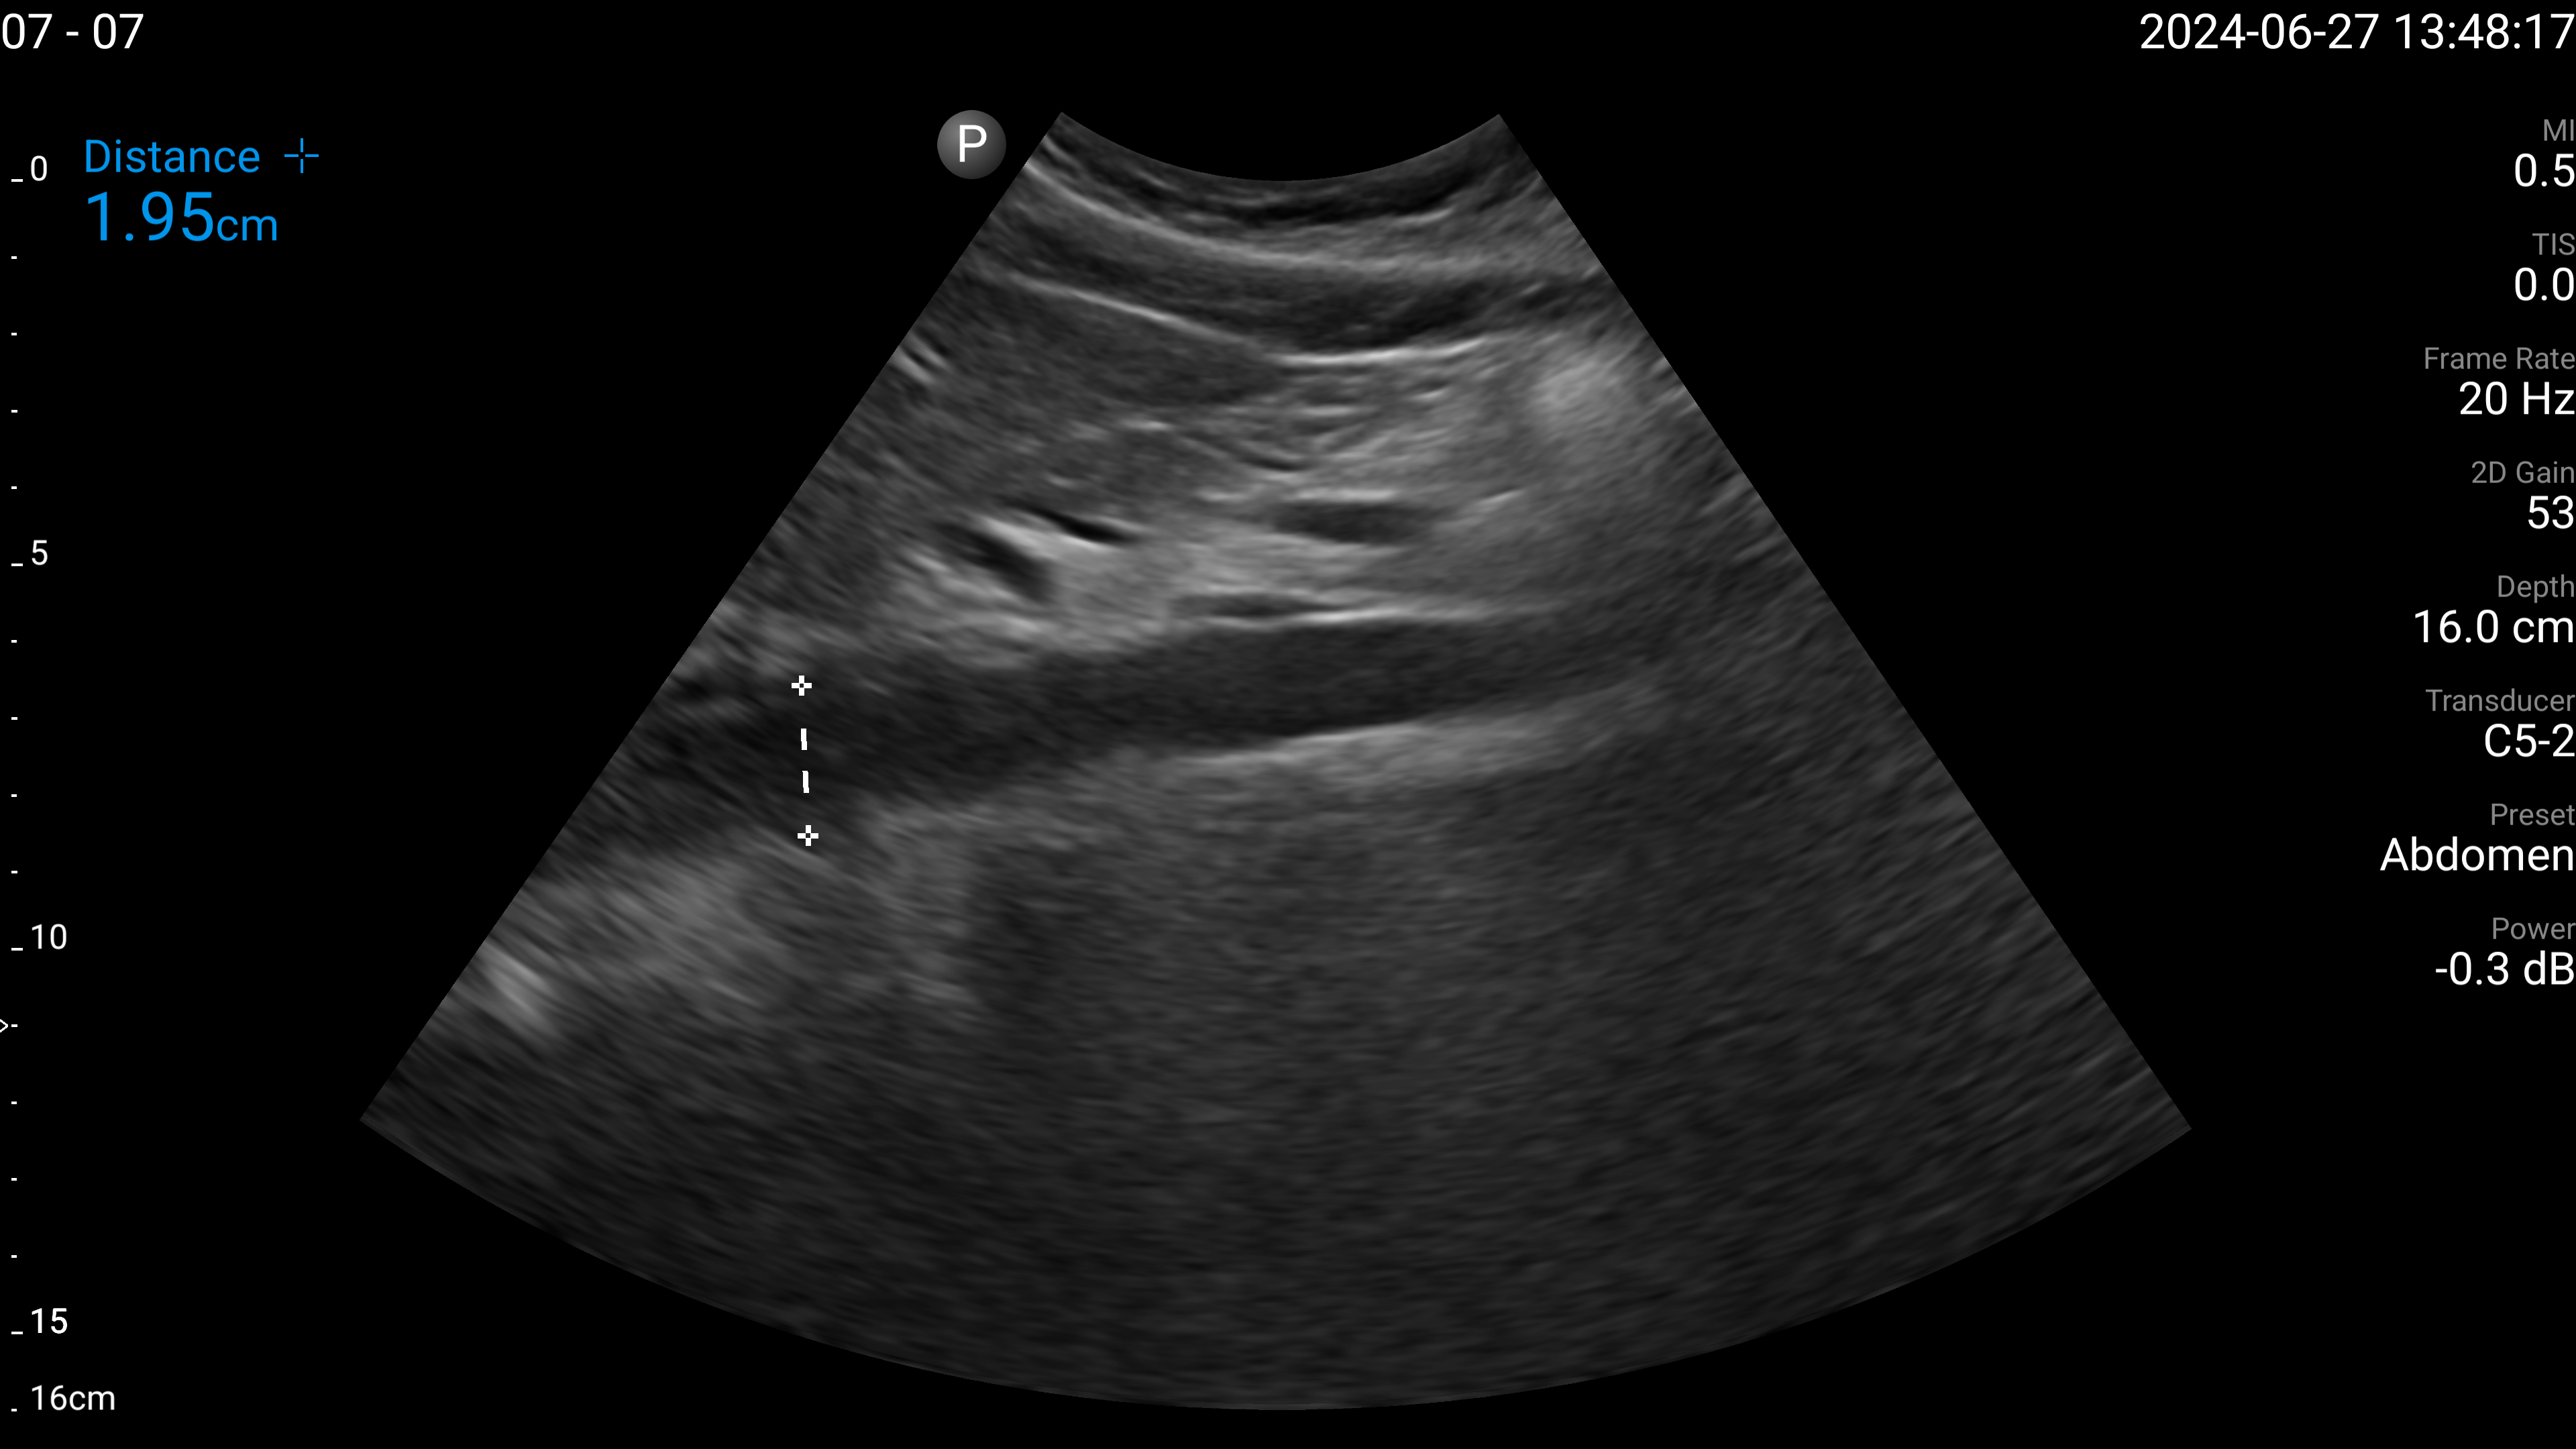

Refer to caption

(a) Proximal aorta with AP diameter.

Figure 4: Examples of the target US images acquired by the sonographers using the human teleoperation system.

The sonographers completed 11 abdominal US scans, each with 5 target images and measurements for a total of 55 images. An example image of each of the targets acquired during these tests is shown in Fig. 4. After completing the scans, two radiologists scored the images based on quality, including identifying targets that could not be seen or were not captured (which were given a score of 0). The distribution of these scores is illustrated in Fig. 5. The first radiologist identified 4 out of the 55 targets as not visible, while the second radiologist identified 6 out of 55 as not visible. Combined, this accounted for 7 unique targets that at least one radiologist considered missing. Of these missing targets, three were not captured due to large amounts of bowel gas and body habitus while one was seen but the sonographer did not capture and save the image. When excluding all the missing targets, the images obtained a mean score of 4.28±0.95plus-or-minus4.280.954.28\pm 0.95 out of 5 and 91.7% of the images were scored 3 or higher by both radiologists. A score of 3 or higher indicated the image quality was sufficient for basic image interpretation. 31.3% of the images were scored 5 by both radiologists, indicating the image quality was good and meaningful image interpretation was easy.